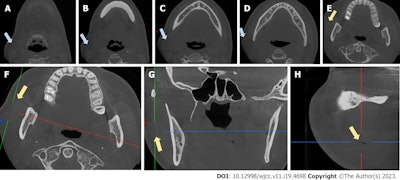

Coronal views of CBCT scans (A-E) show swelling. The CBCT scan shows an air-filled fissure between the masseter muscle and soft tissue (F-H) . The blue arrows indicate swelling, while the yellow arrows indicate the fissure. Images courtesy of Sun et al. Licensed by CC BY 4.0.

Fortunately, the woman’s prompt diagnosis and treatment prevented cervical subcutaneous emphysema in the angle of the retromandibular vein from developing into a deep space infection, air embolism, cranial nerve palsy, or worse, according to a report published in the World Journal of Clinical Cases.